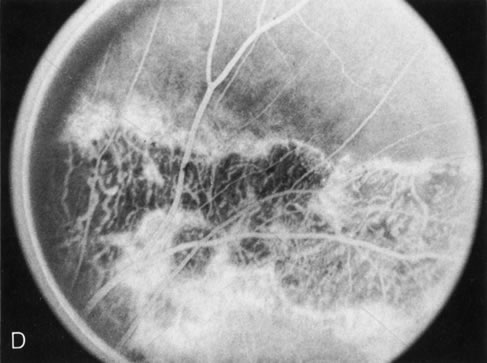

Of more clinical importance is the role of FA in the diagnosis and treatment of cystoid macular edema (CME) (Fig. 1C and D). Stereoscopic FA indicates that the leakage, which may be diffuse or have the typical petaloid stellate appearance of CME, can come from the perifoveal retinal capillaries, from the choroid through the RPE, or from a combination of both sources.4 With the recent suggestion that CME in RP may be successfully treated with acetazolamide,5, 6 FA is thus important to document the diagnosis of CME, establish the origin(s) of leakage, and follow patients during and after therapy.